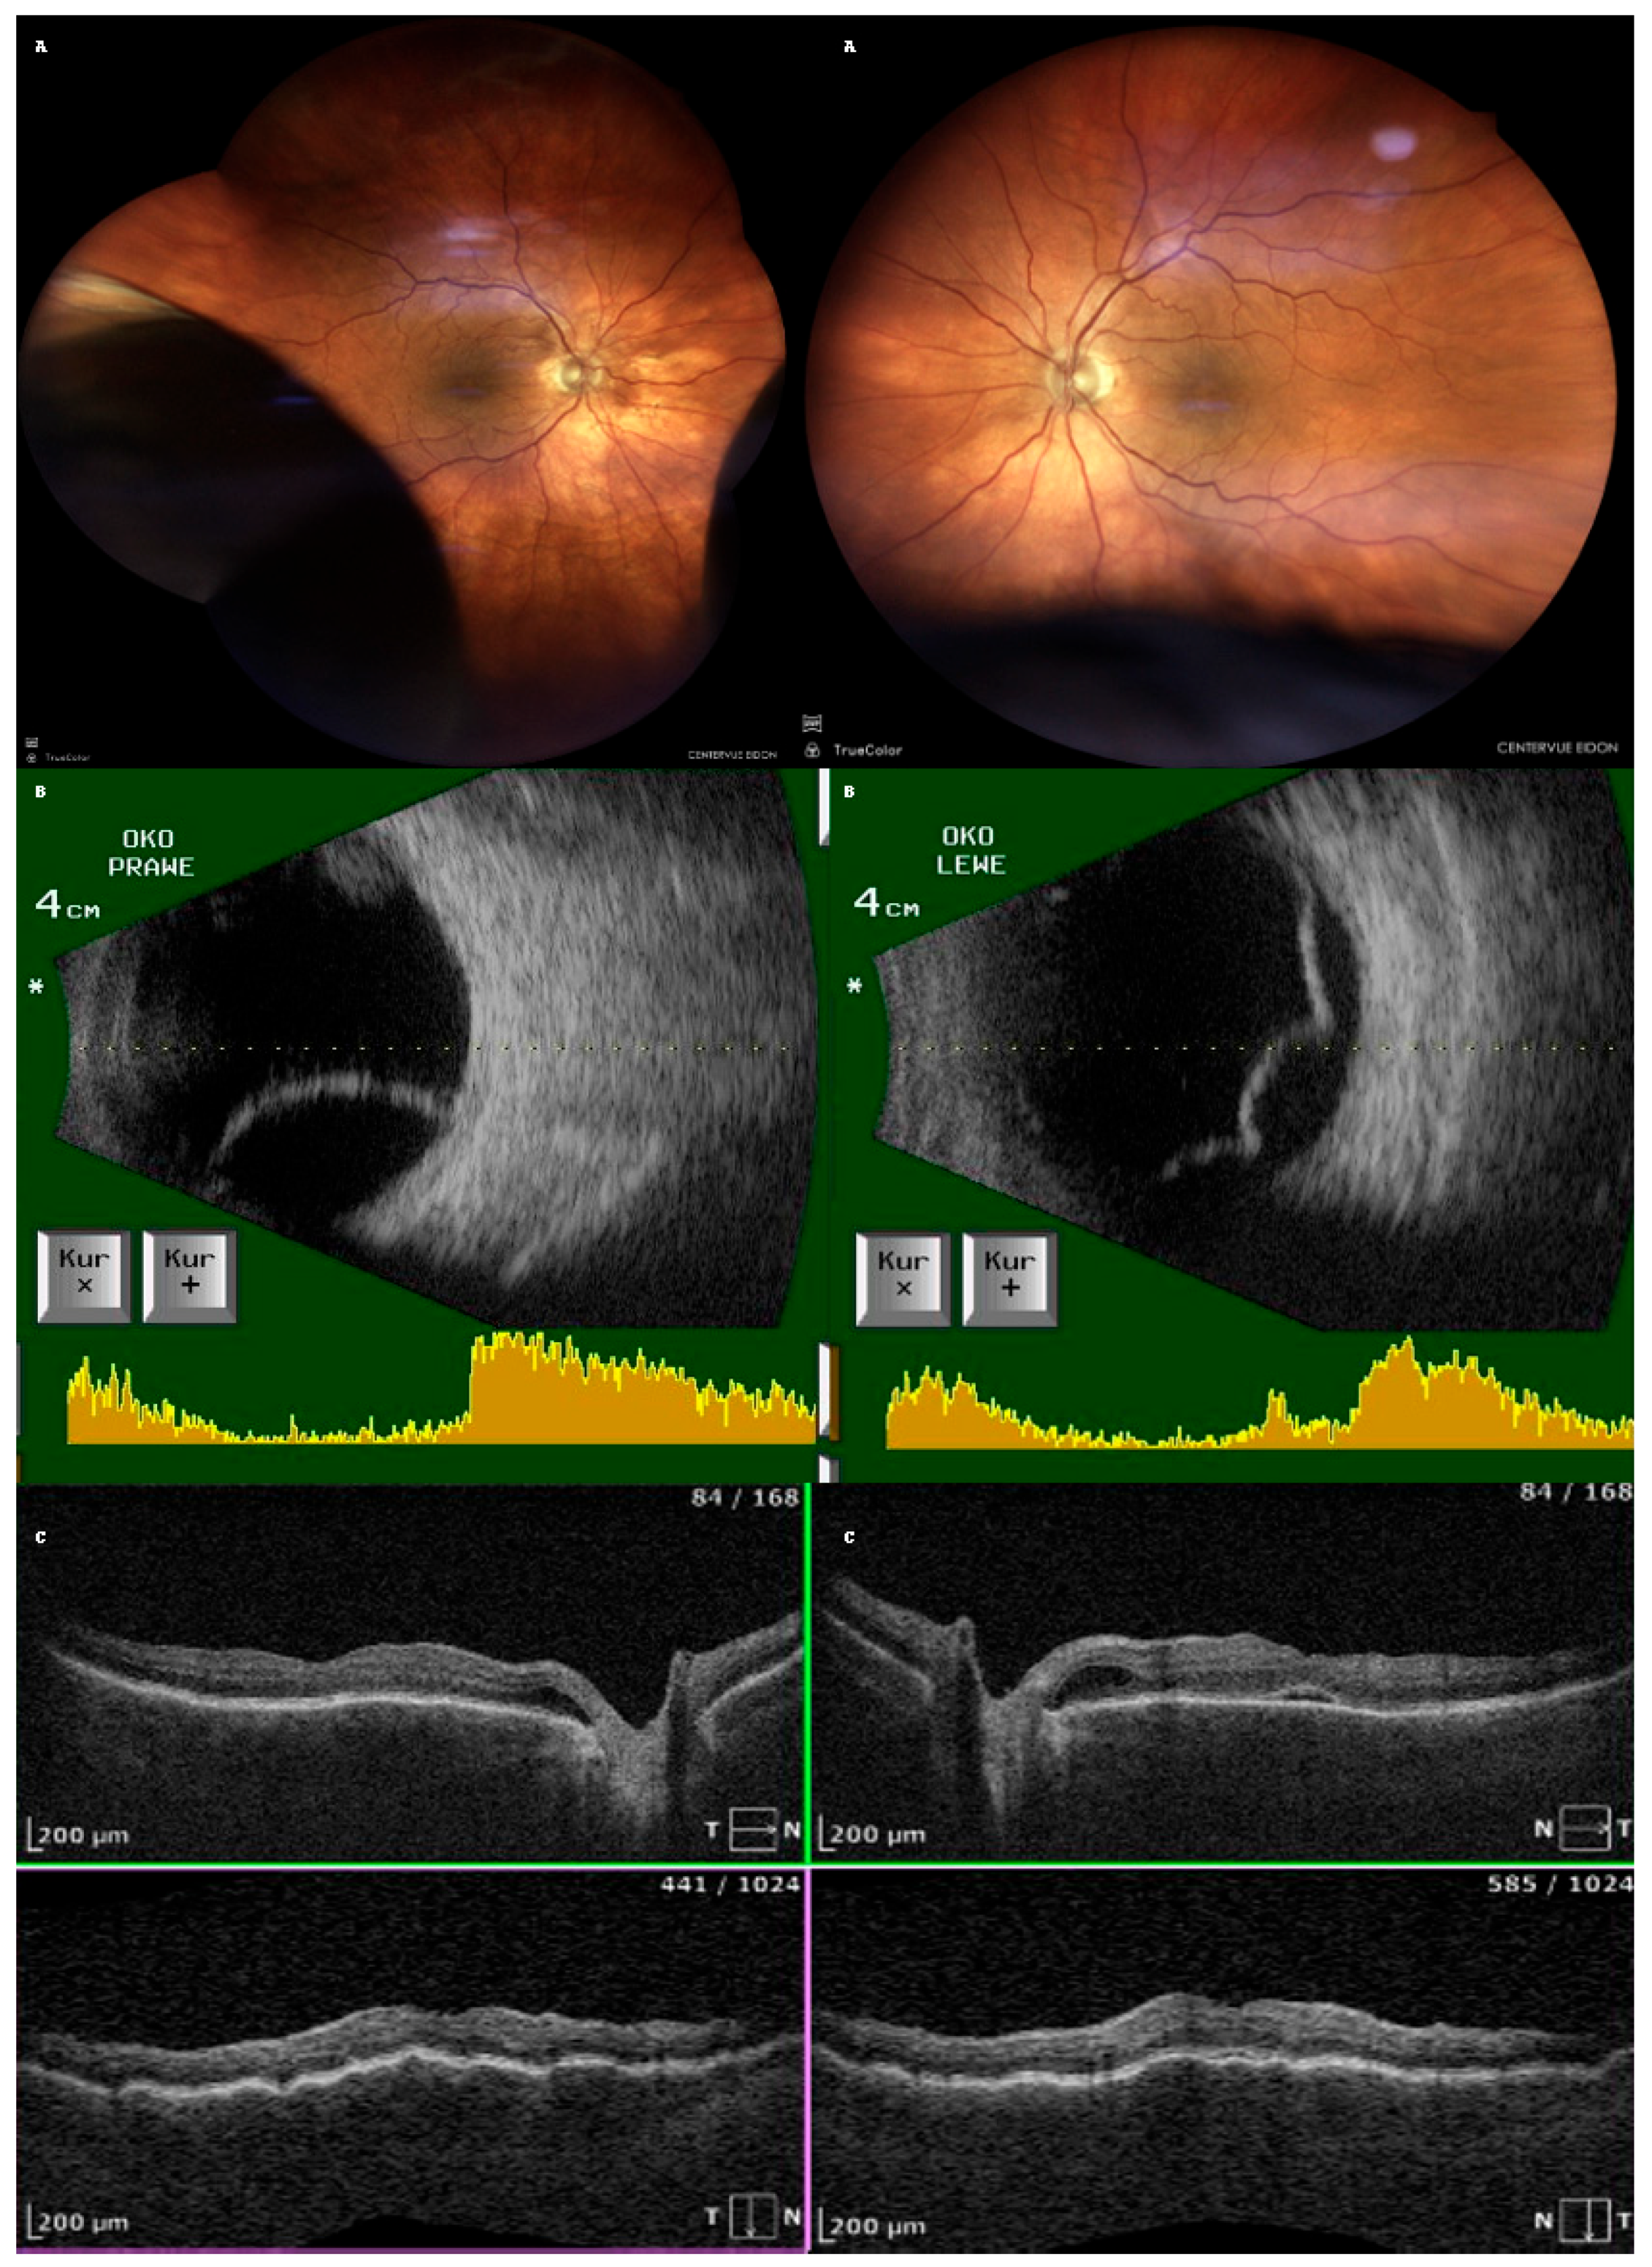

An 87-year-old Caucasian male was admitted to our clinic with sudden, painless vision loss of his left eye. His medical history was unremarkable except for uneventful cataract surgery in both eyes two months prior. Two months postoperatively, he developed macular edema in the left eye, which was confirmed on optical coherence tomography (OCT, SOCT-Copernicus, Revo NX, Software version 11.5.1, Optopol Technology Ltd., Zawiercie, Poland) (Figure 1). Treatment for PCME was initiated with topical pranoprofen and oral acetazolamide (250 mg twice a day).

After one week of treatment for PCME, the patient returned with a bilateral vision decline. Fundoscopy revealed bilateral, infero-temporal and infero-nasal choroidal detachment (fundus photo with the use of confocal scanner Eidon, CenterVue, ICare Finland Oy, Vantaa, Finland); Figure 2A. Ultrasound examination confirmed bullous choroidal detachments (Ultrasound B-scan, Pirop, Echo-SonSA, Puławy, Poland) in both eyes (Figure 2B). OCT scans showed subretinal fluid (SRF) and choroidal folds in both eyes but complete resolution of the macular edema in the LE (Figure 2C). The intraocular pressure (IOP) measured with Tono-Pen AVIA (Reichert Technologies, Reichert Inc., Depew, NY, USA) was 16 mmHg (RE) and 14 mmHg (LE).

Figure 2. Imaging of choroidal effusion in both eyes: (A): Fundus photographs showing bullous choroidal detachment; (B): ultrasonography showing more pronounced detachment in the right eye; A scan is depicted on the bottom of the B scan (yellow diagram), top of the ultrasound probe is indicated as (*) (C): OCT showing choroidal folds and resolution of PCME in the left eye.